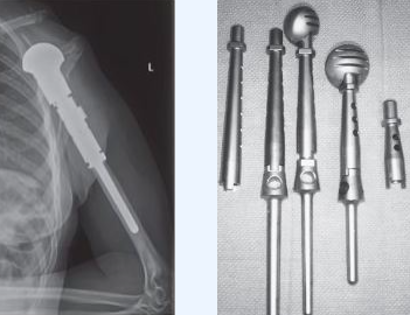

A total humerus prosthetic replacement is a procedure that involves removing a tumor, usually malignant or benign aggressive, of the entire arm bone/humerus and in most instances replacing the bone with a special customizable total humerus tumor prosthesis.

The tumor prosthesis is inserted. This prosthesis is sized and built during the surgical procedure then implanted. Then the prosthesis is cemented into the bone and is safely secured in place.